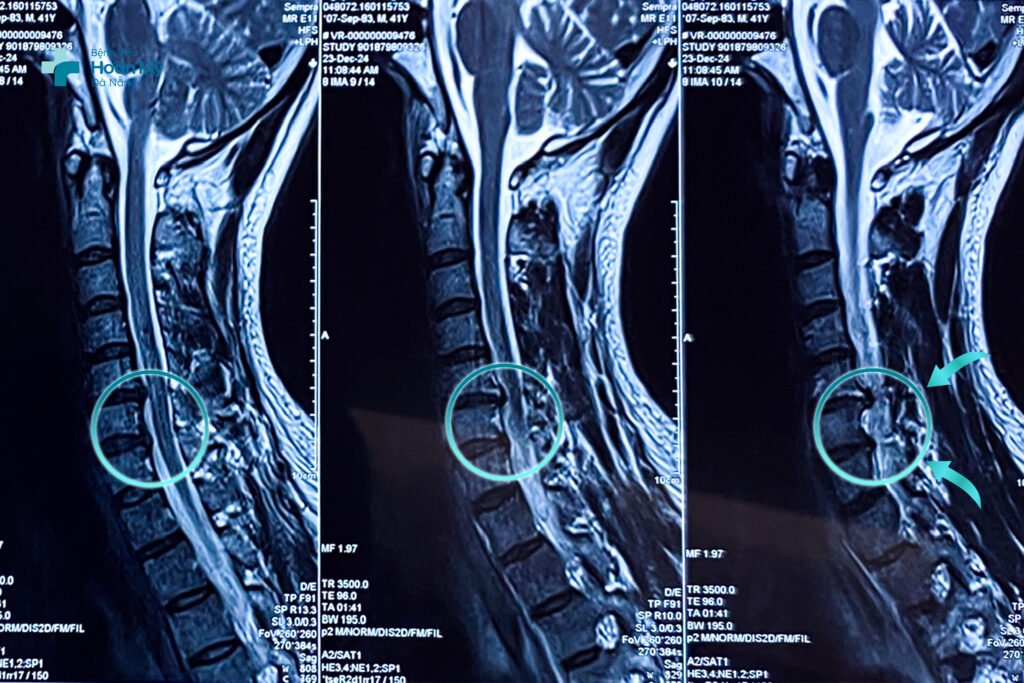

TS.BS. Lê Đình Huy Khanh – Trưởng khoa Ngoại Thần kinh – Cột sống, Bệnh viện Hoàn Mỹ Đà Nẵng chia sẻ: qua thăm khám, chụp MRI cột sống cổ có hình ảnh thoát vị đĩa đệm cổ C5-6 và C6-7 bên trái – phù tủy mức tương ứng. Người bệnh có chỉ định phẫu thuật ACDF (Anterior Cervical Dicsectomy and Fusion) lấy nhân thoát vị đĩa đệm và hàn xương cột sống cổ lối trước dưới sự hỗ trợ của kính vi phẫu, màn hình tăng sáng trong phẫu thuật, máy mài cao tốc nhằm giải phóng đĩa đệm chèn ép tủy cổ, rễ thần kinh cột sống, nhằm tránh nguy cơ liệt tay trái và cải thiện chất lượng cuộc sống.

Thoát vị đĩa đệm cột sống cổ hiển thị rõ trên MRI